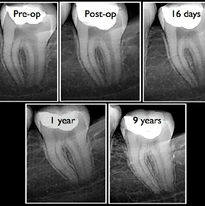

Local anaesthesia is given and the tooth is isolated with a rubber dam (a special hygienic rubber sheet) to prevent contamination of the tooth from saliva and to protect the patient from accidently swallowing any chemicals or foreign objects. An opening is made through the chewing surface of the tooth to gain access to the root canal system. The pulp tissue is painlessly removed with special endodontic files. Root canal lengths are measured with an electronic locator and confirmation takes place by means of an x-ray. The root canal/s are cleaned, disinfected, enlarged and shaped with rotary instruments and chemicals. The root canal/s is filled with a rubber substance called gutta percha that is plasticised with heat to obtain a three dimensional filling of the prepared root canal spaces. The tooth is then restored with a foundation filling and the tooth is ready for the referring dentist to place a crown on the tooth.